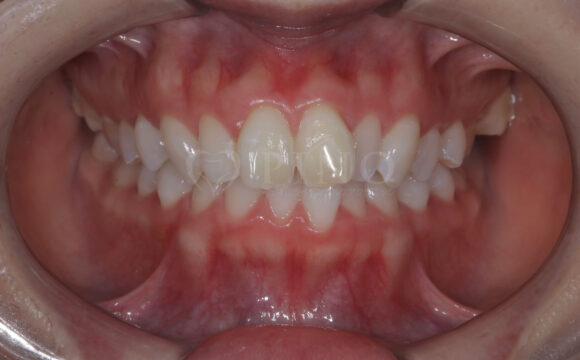

症例4:噛み合わせが深く、下の歯が見えないのが気になる(10代女性)

主訴 噛み合わせが深い、下の歯が見えない 診断名 過蓋咬合(かがいこうごう) 治療方法 マウスピース全顎矯正 抜歯 なし オルソパルス なし 治療期間 1年1ヶ月 費用 746,000円 副作用・注意点 矯正後の後戻りを防ぐためリテーナーの使用が必要となる -